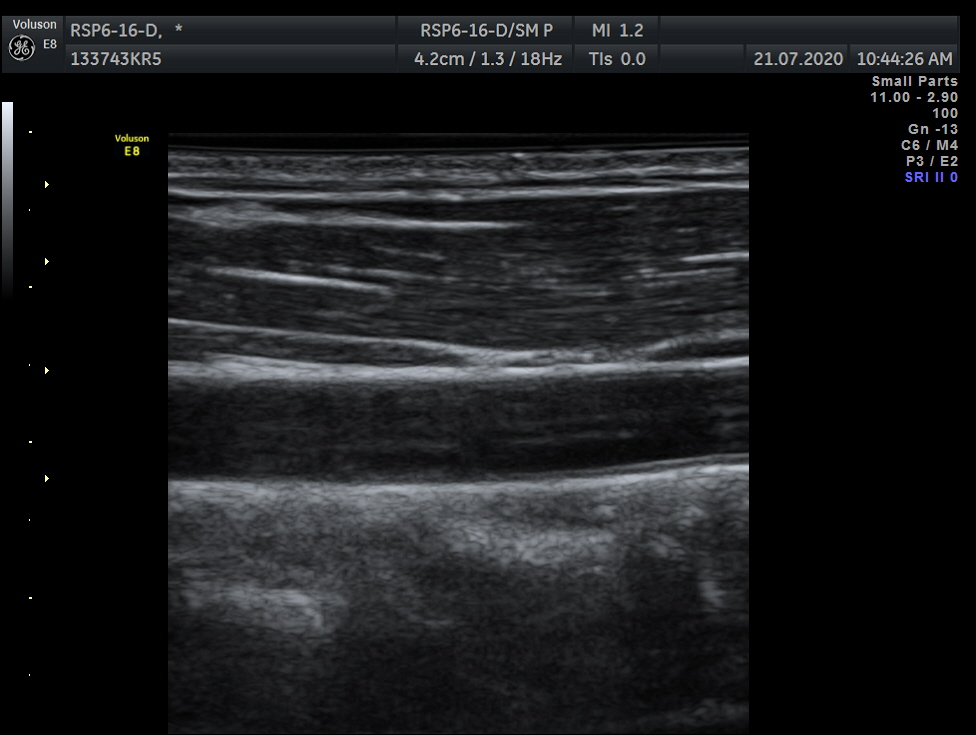

Breast, Small parts, Vascular and Musculoskeletal

Frequency Range: 18 – 6 MHz

GE RSP6-16-D 3D/4D Linear for Breast, Small parts, Vascular and Musculoskeletal

| Type of examination 3D/4D | |